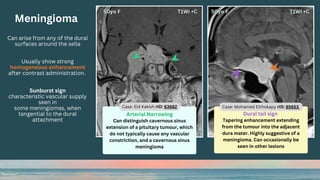

Meningioma

Can arise from any of the dural

surfaces around the sella

Usually show strong

homogeneous enhancement

after contrast administration.

Sunburst sign

characteristic vascular supply

seen in

some meningiomas, when

tangential to the dural

attachment

Arterial Narrowing

Can distinguish cavernous sinus

extension of a pituitary tumour, which

do not typically cause any vascular

constriction, and a cavernous sinus

Case: Eid Kakish rID: 63682 Case: Mohamed Elthokapy rID: 85653

Dural tail sign

Tapering enhancement extending

from the tumour into the adjacent

dura mater. Highly suggestive of a

meningioma. Can occasionally be

seen in other lesions